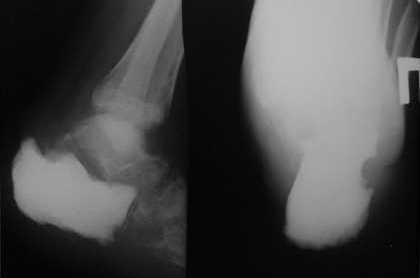

Хондросаркома пяточной кости |

Б-й Т. 25 лет. Обратился впервые 04.11.09 с новообразованием пяточной кости. Выполнена биопсия, установлен диагноз: высокодифференцированная хондросаркома. ----- произведена экзартикуляция пяточной кости, замещение дефекта цементным спейсером. После операции раны зажили первично. Планировались артродезы голеностопного сустава, таранно-ладьевидного и ауто-аллопластика пяточной кости. В январе онкологами проведён курс лучевой терапии пяточной области и к концу курса, через 1,5 месяца после операции, открылся точечный свищ в середине рубца по медиальной поверхности пяточной области. Отделяемое серозное. Конечность не нагружалась. Госпитализирован в отделение 13.03.10. Взят посев (в работе). Хотелось бы узнать мнения коллег по дальнейшей тактике ведения больного.